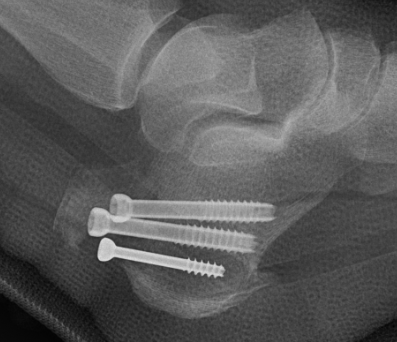

Xrays

Screw fixation

Poor bone quality

- 2 - 3 screws

- bicortical fixation

- fully threaded screws for extra fixation

- consider washers

- dont but screw heads too close to each other or fracture (risk of comminution)

Fixation failure with screws